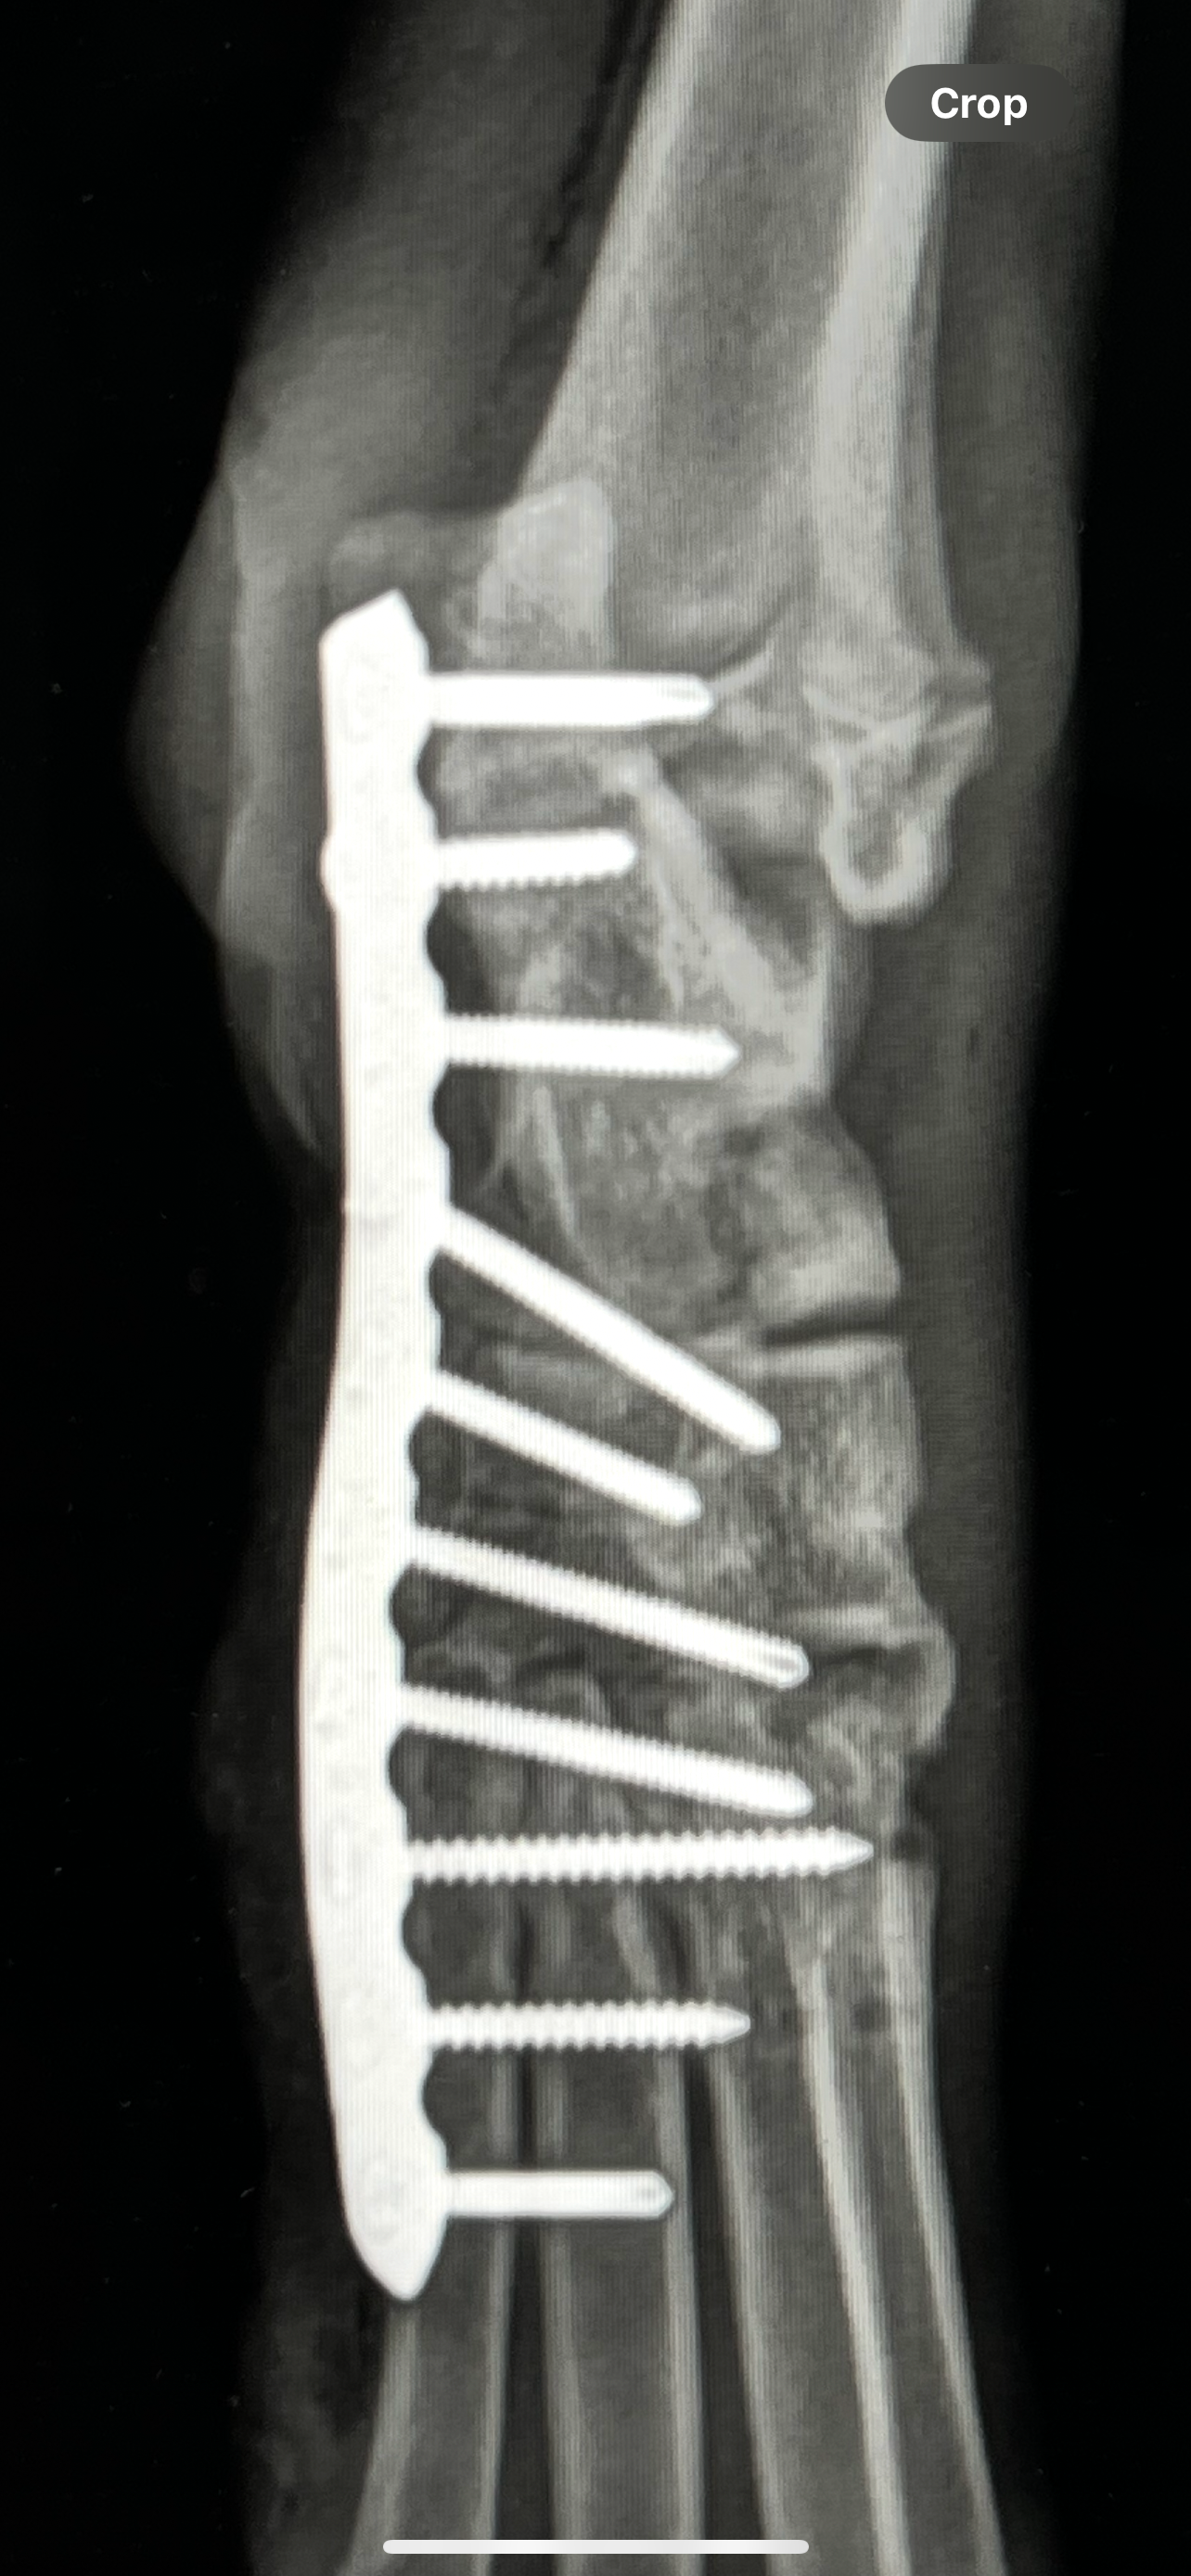

Gemma is the sweet rescue who was run over by an electric bike and left on the street for 4 days. A metal plate was placed in her leg to save it. Since then, she has grown from 30 lbs to 50 lbs, and the hardware that once helped her heal is now harming her.

Last month, Gemma re-injured the same leg, and she now has visible swelling and irritation around the area. After examining her, the vet has recommended immediate plate removal to prevent worsening pain, infection, and permanent damage.